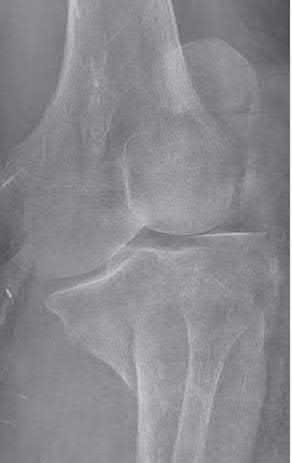

Question 16

During a posterior-stabilized total knee arthroplasty, the surgeon evaluates the gaps using trial components.

The assessment demonstrates that the extension gap is perfectly balanced and rectangular, but the flexion gap is excessively tight. What is the most appropriate isolated next step to balance the knee?

Explanation

If the flexion gap is tight but the extension gap is balanced, the surgeon must alter the flexion gap without affecting the extension space. Downsizing the femoral component (using the same posterior referencing guide, or using an anterior referencing system) translates the posterior condylar surface anteriorly, effectively increasing the flexion space while leaving the distal femoral resection (extension gap) unchanged.